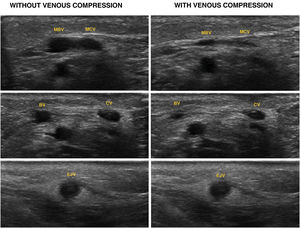

This is the case of a patient admitted to the intensive care unit with signs of right sided pneumonia. A peripherally inserted central catheter (PICC) is cannulated for intravenous treatment. The thoracic x-ray performed reveals that the catheter does not land in the right atrium following a trajectory at clavicle level (Fig. 1). Six days after admission the PICC is removed revealing the presence of neck cellulitis at left jugular vein. The vascular ultrasound performed confirms the presence of venous thrombosis from the cannulation area of the PICC in the mid left cephalic vein (LCV) progressing through the cephalic vein (CV) until it reaches the external jugular vein (EJV) through a segment of supraclavicular anomalous venous communication (AVC) (Figs. 2 and 3).